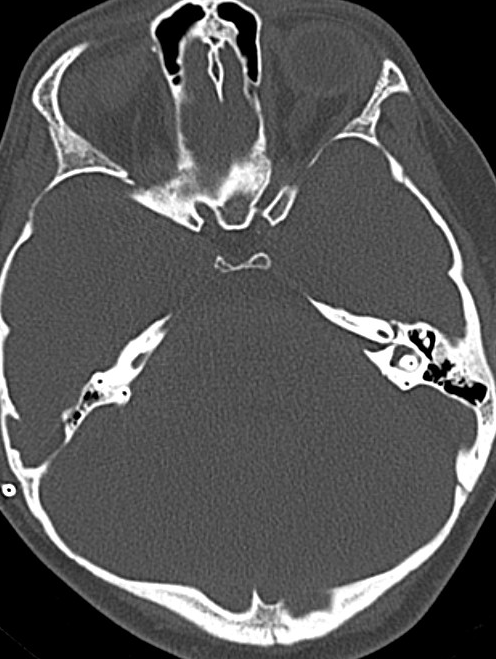

Sharing with the group the calvarial thickening and canal narrowing in my pt. It can be very severe. Please share the canal size too.

I saw a patient (the only one I've seen) with osteopetrosis. He's an 11-year-old boy. His vision is limited to counting fingers to two feet in his right eye (OD), and he has light perception in his left eye (OS). He shows no signs of intracranial hypertension, and his optic nerves are extremely pale. The CT scan of his head clearly shows compression of the optic canal; it's so narrow it's almost imperceptible. I requested a neurosurgical consultation to see how it could be decompressed, but unfortunately, they said it wasn't possible due to the significant thickness of his bones.